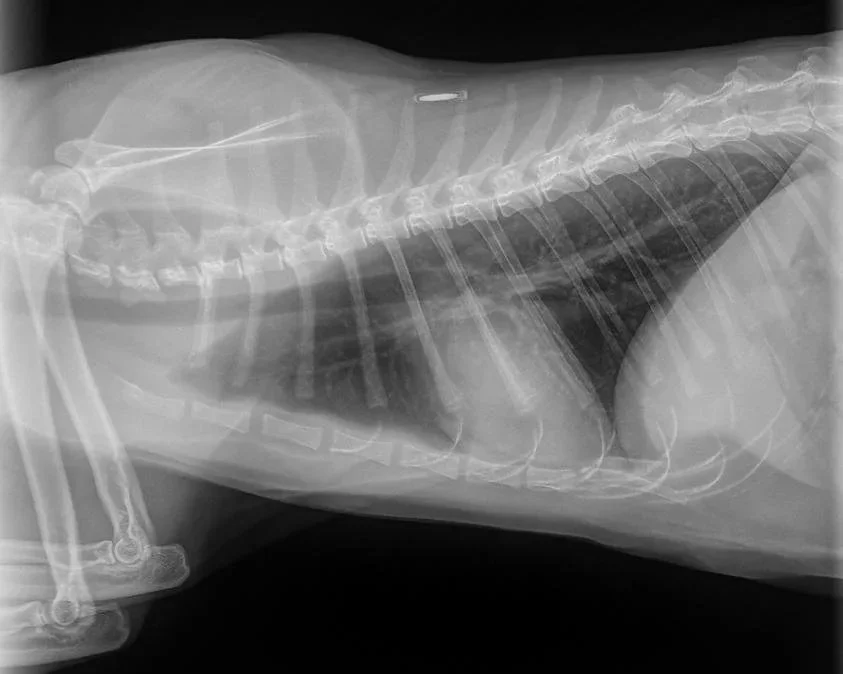

• Feline Asthma: By injecting activated stem cells, we can help calm the overactive immune response in the lungs. Research suggests that stem cells can reduce airway hyper-responsiveness and lung remodeling in asthmatic cats (MDPI, 2023).